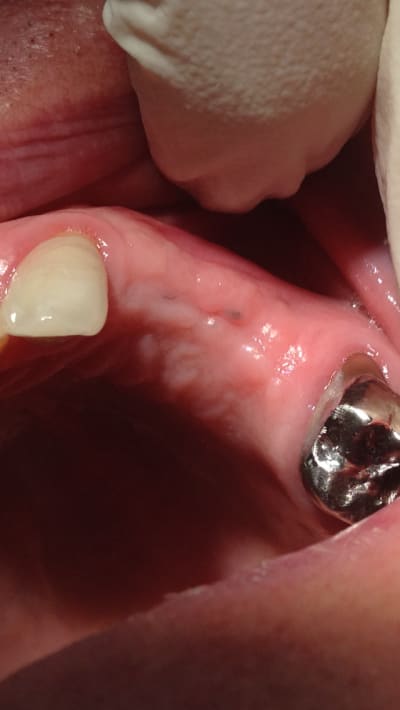

Cicatrisation à une semaine après mon cas , quasi pas de douleur pour le patient :

https://www.dropbox.com/s/1vc1v2sgawc8tnp/IMG_0616.JPG?dl=0

l adan

13/12/2016 à 10h57

porte t'il un provisoire ?

Utilisateur banni

14/12/2016 à 20h45

Surtout pas